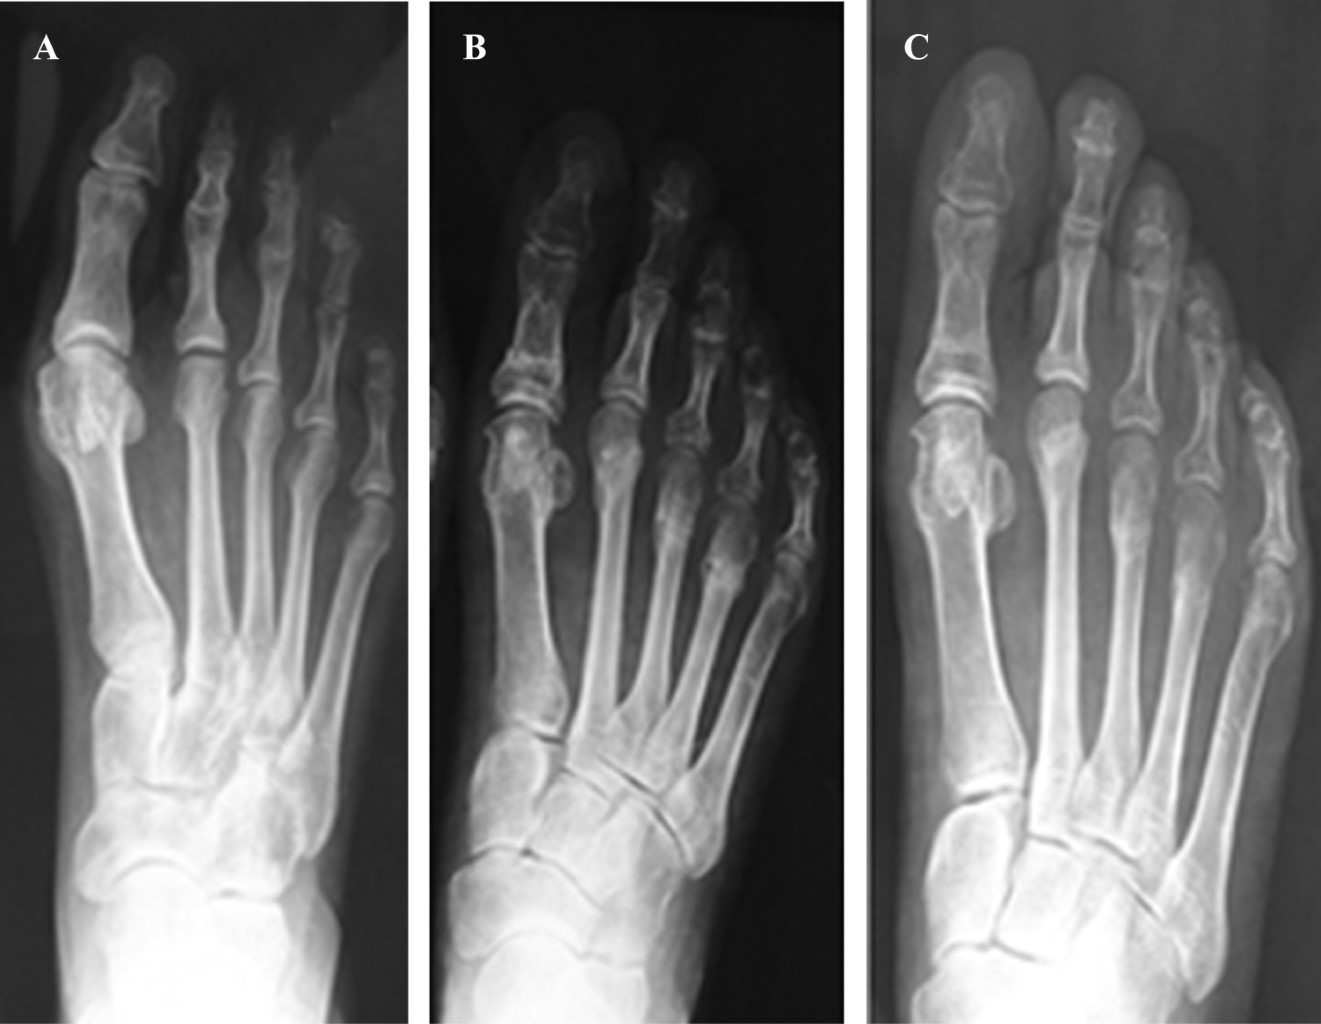

En cuanto a las mediciones radiográficas, estas se toman siempre en proyecciones dorsoplantar y lateral que se toman con los pacientes de pie y con apoyo (Figura 3). Los valores de las mediciones tanto prequirúrgicas como postquirúrgicas se pueden ver en la Figura 4. Nuestros resultados reflejan una disminución en promedio de 2o del ángulo intermetatarsal. Estos valores reflejan una variación de los ángulos consistente con las correcciones logradas en otros estudios mediante el uso de osteotomías distales.8,9

Figura 3